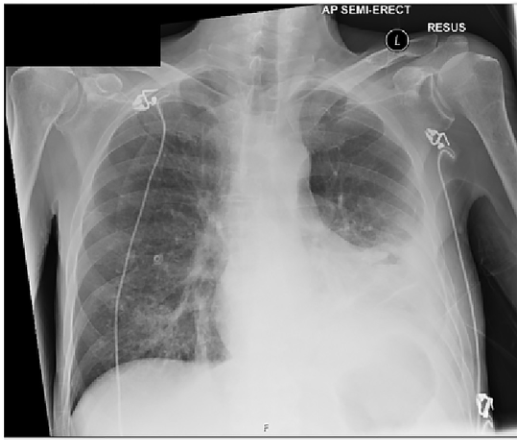

肺分画症 画像診断まとめ->画像所見 : 胸部単純 x 線写真正面像では右下肺内側が暗くなっており、右心第 2 弓の輪郭が不明瞭(シルエットアウト)。 側面像では肺門部から前肋横角に向かう紡錘形の陰影(↓)がみられる。 >診断 : 中葉無気肺 >解説 : 無気肺化した中葉は正面単純写真では右心第 2 弓を底辺と 肺分画症手術後、病理診断で肺腺がん発覚。 StageⅠB期 33歳。突然の「がんサバイバー」として病気と向き合う。 手術後の経過と備忘録。自分の気持ちを整理するためにありのままの思いをつづってみます。 日常記録も書きます。気まぐれ不定期更新です。

呼吸器領域の画像解剖と症例 兵庫医科大学放射線科 小林薫 第4回兵庫県放射線技師会読影セミナー 平成28年12月17日 本日の内容 •胸部単純x線写真について –基本的事項 •胸部ct:読影に必要な解剖について –肺野区域解剖 •各種症例の画像と読影のポイント –肺炎 –胸膜/胸壁疾患 –その陰嚢水腫、Nuck水腫 臍腸管遺残・尿膜管遺残 胚細胞性腫瘍 肺分画症 肥厚性幽門狭窄症 ヒルシュスプルング病 副耳 腹壁破裂 便秘 肺分画症の画像所見 肺底部に多房性嚢胞〜充実腫瘤 として認められる。 大動脈から分岐する異常血管を見つける ことが診断に有用。 ご案内 腹部画像診断を学べる無料コンテンツ 4日に1日朝6時に症例が配信され、画像を実際にスクロールして読影していただく講座です。現状無料公開

縦隔腫瘍、CCAM、肺分画症 著者 Author(s) 藤岡, 一路 / 芳本, 誠司 掲載誌・巻号・ページ Citation 周産期の画像診断 第二版,周産期医学 / 周産期医学編集 委員会編, Vol 43, 13 増刊号4486 刊行日 Issue date 1312 資源タイプ Resource Type Journal Article / 学術雑誌論文 版区分 Resource Version publisher 権利 Rights DOI肺分画症 硬化性血管腫 肺動静脈瘻・奇形 特発性肺線維症(ipf) 60歳過ぎた男性 60%以上 ほとんどの治療法は無効 死亡率は5年で50~70% 呼吸細気管支炎関連間質性肺疾患(rbild) 40~50歳 (やや男性に多い) 90%以上 禁煙、ステロイド 死亡はまれ 上に戻る 胸部レントゲン写真の所見別VR 画像を作成することで、さらに血管走行の詳細がはっきりする。 >診断 : 肺分画症( intralobar pulmonary sequestration ) >解説 : 分画肺は大動脈から分岐する異常動脈から血流を受け、以下の 2 型に分類される。原則として正常気管支とは交通がない。

日々の症例 143 肺分画症 Intralobar Pulmonary Sequestration

症例0 肺葉内肺分画症 Ct 症例 肺 X線写真